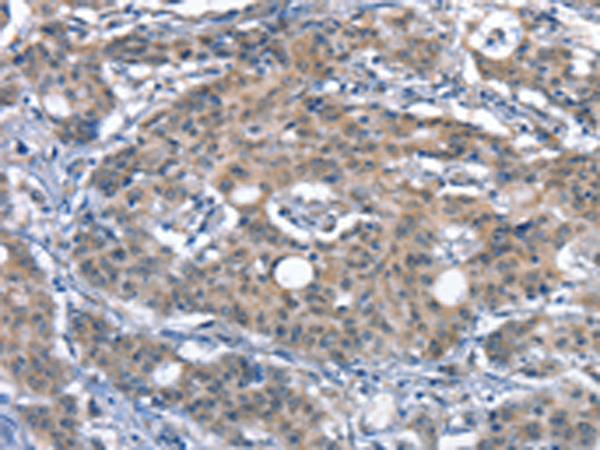

分类: 科研抗体货号: P11269别名: IRF; SMRZ; MURF1; MURF2; RNF28应用: WB,IHC反应种属: Human, Rat